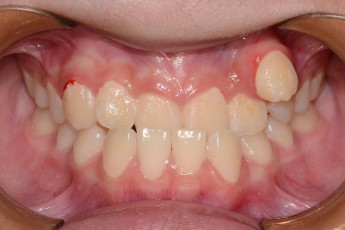

Before & After

Before

After